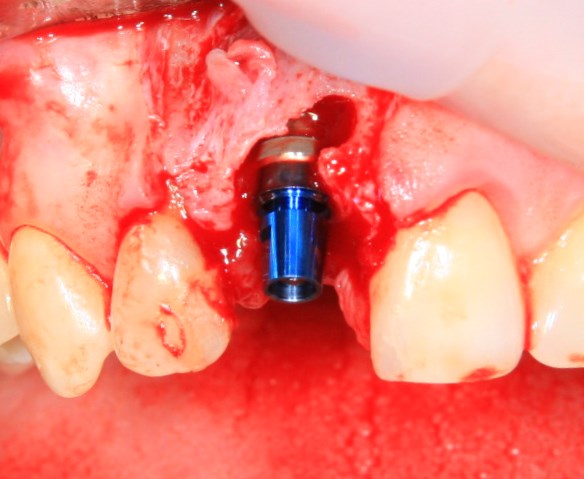

Немедленная имплантация — оптимальное решение в любой клинической ситуации